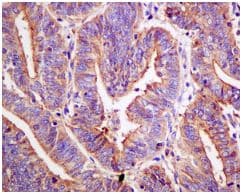

Anti-FOXO3A (phospho S253) antibody [EPR1951(2)] - BSA and Azide free(ab240127)

Rabbit Recombinant Monoclonal FOXO3A phospho S253 antibody. Carrier free. Suitable for IHC-P, Dot, WB and reacts with Human, Synthetic peptide samples. Cited in 2 publications.